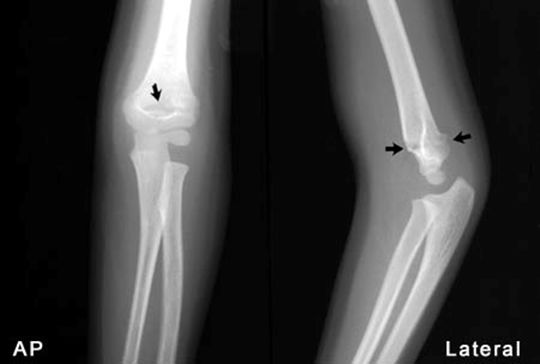

肱骨髁上骨折

疼痛科怎么理疗疼痛科医生、康复理疗科医生、针刀针灸医生应掌握的常见骨科疾病X光片_https://www.jmylbn.com_新闻资讯_第11张